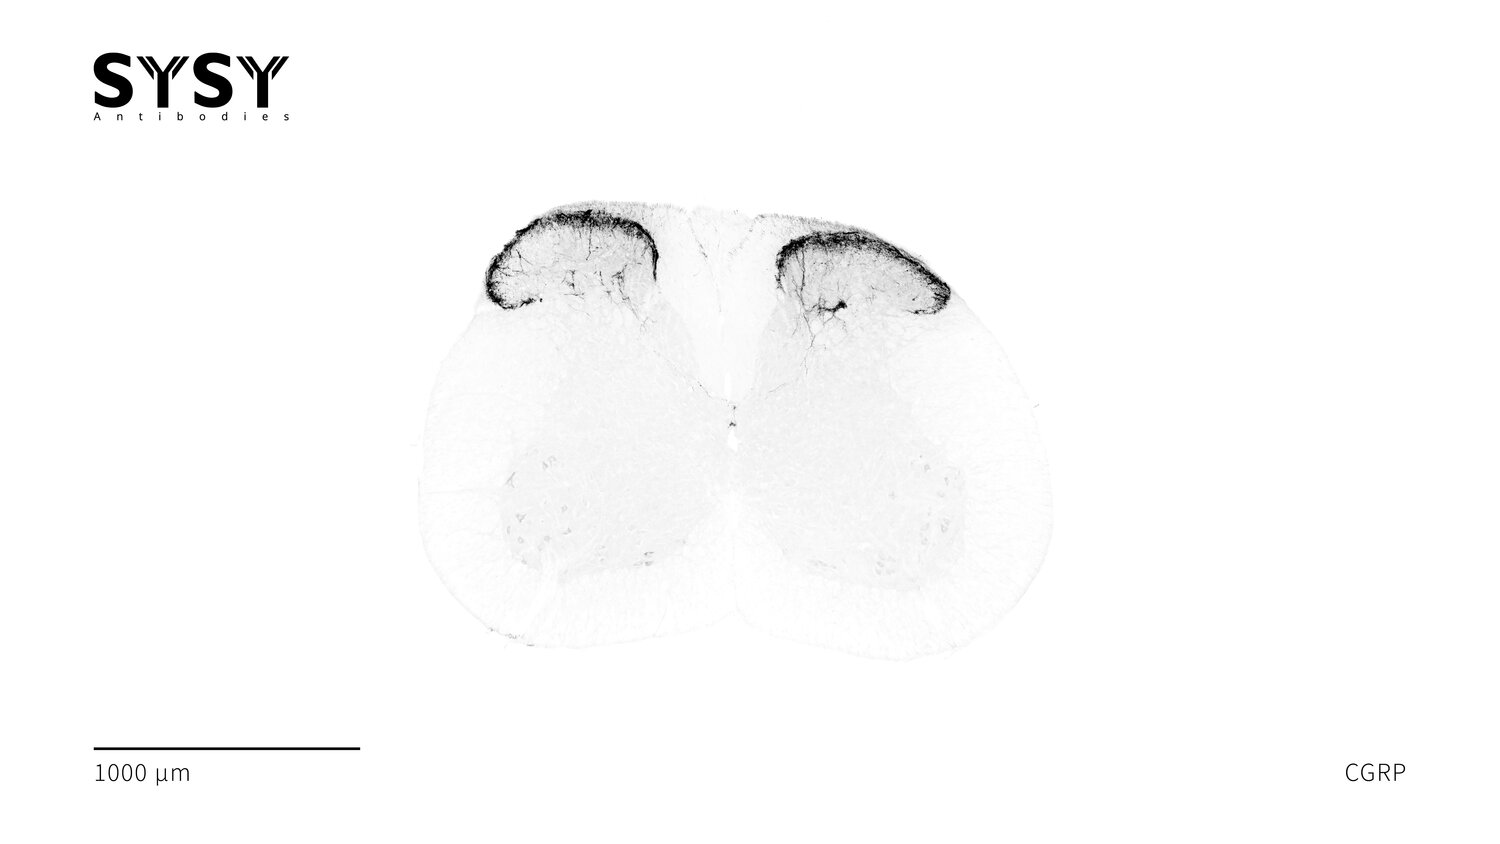

CGRP

Indirect immunostaining of a formaldehyde fixed mouse spinal chord section with guinea pig anti-CGRP antibody (cat. no. 414 004, dilution 1 : 500).